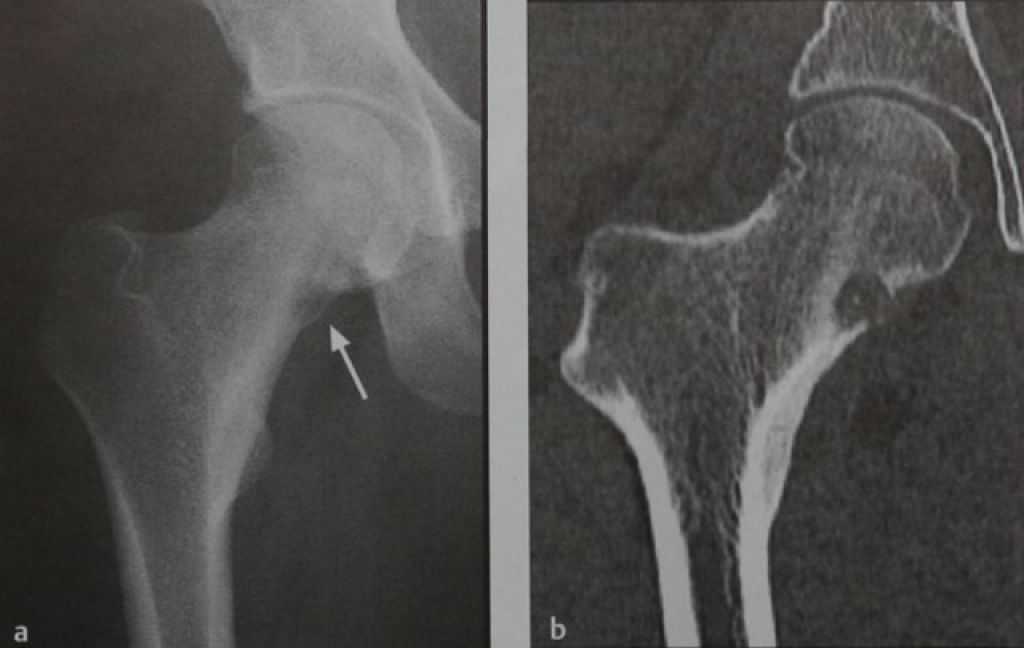

Иллюстрации и снимки, связанные с остеопенией шейки бедра